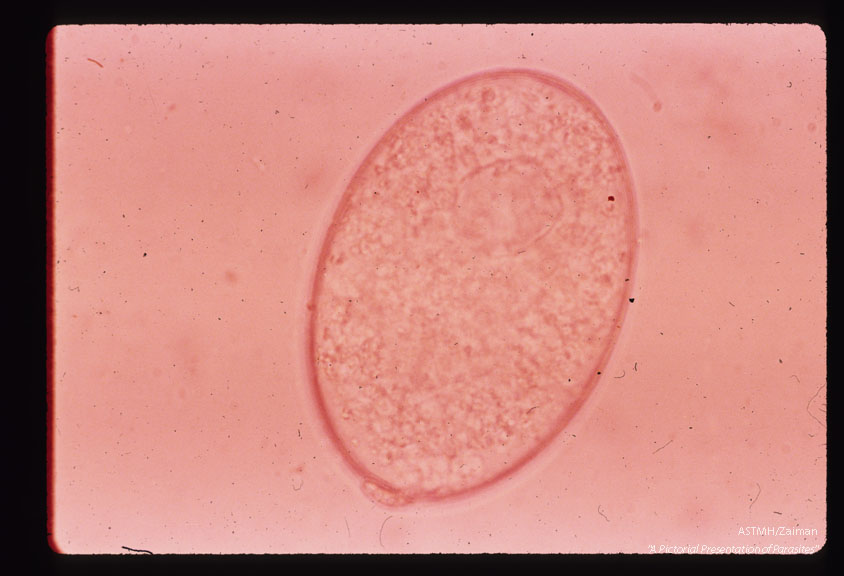

Egg.

Echinococcus malayanum

Description: Egg.